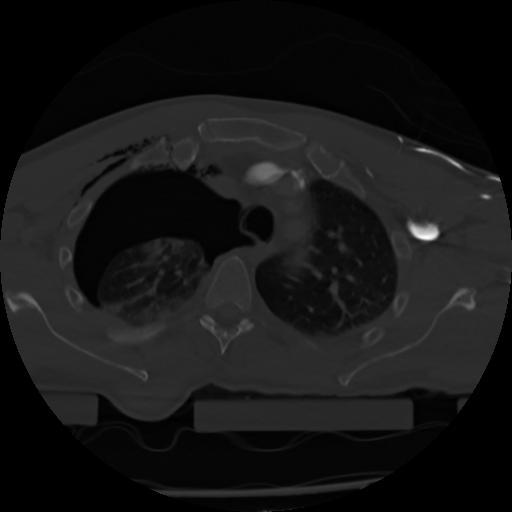

21 ANGIO,CE,Axial,3.0,ANGIO,,